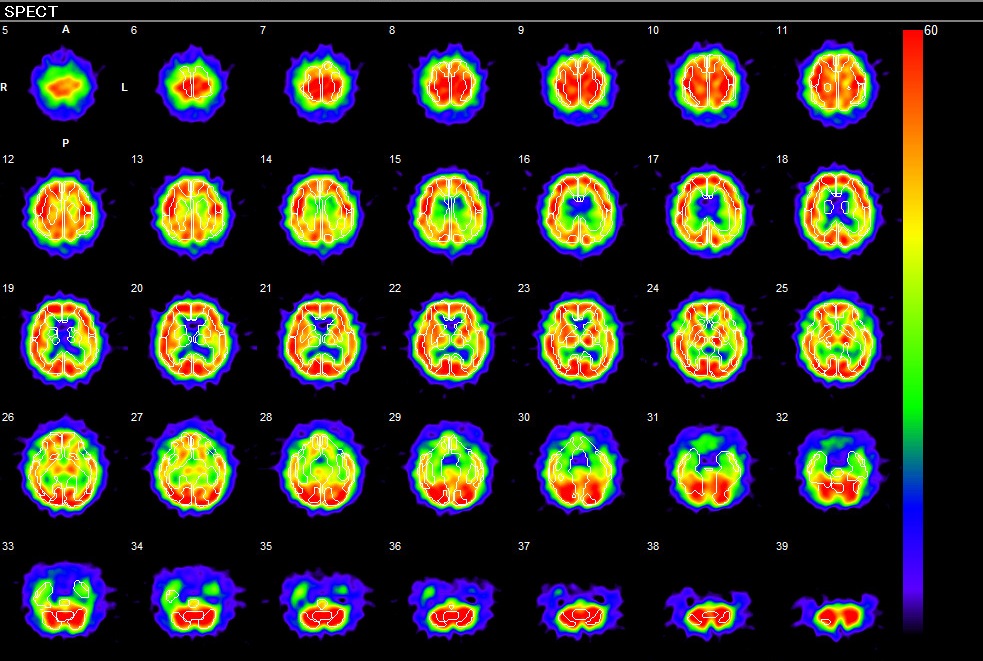

核医学では認知症診療の一つとして脳血流SPECTを施行しています。脳血流SPECTでは脳血流が低下している部位を調べることにより認知症の早期診断や4大原因であるアルツハイマー型認知症やレビー小体型認知症、血管性認知症、レビー小体型認知症、前頭側頭型認知症などを鑑別することが可能です。 かかりつけ医や認知症サポート医の皆様の認知症治療やケアに有意義となる画像を提供しています。

アルツハイマー型認知症:後部帯状回・楔前部・頭頂葉の血流低下を認める